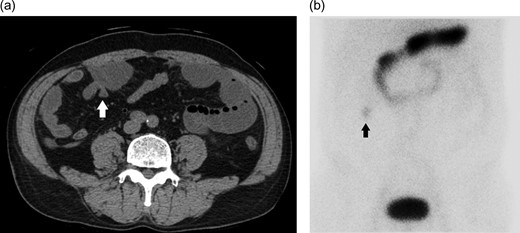

Abdominal computed tomography (CT) showed slight intestinal dilation (Fig. 1a). No abnormal findings were noted on blood biochemical analysis, other than the white blood cell count, C reactive protein levels, and a mild inflammatory response. On admission, a diagnosis of bowel obstruction was made. CT at the time of diagnosis showed an obstruction of the upper right quadrant of the small intestine (Fig. 1a), while ectopic gastric mucosal scintigraphy revealed abnormal accumulation in agreement with the structure identified by CT (Fig. 1b).

a) A structure that becomes small blind and has blind end so that it protrudes from the small intestine (white arrow). (b) Accumulation in the area close to the structure pointed out by scintigraphy (black arrow).